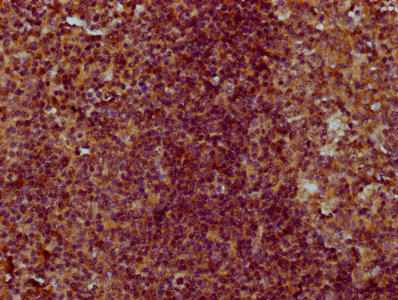

IHC image of CSB-PA005641LA01HU diluted at 1:300 and staining in paraffin-embedded human tonsil tissue performed on a Leica BondTM system. After dewaxing and hydration, antigen retrieval was mediated by high pressure in a citrate buffer (pH 6.0). Section was blocked with 10% normal goat serum 30min at RT. Then primary antibody (1% BSA) was incubated at 4°C overnight. The primary is detected by a biotinylated secondary antibody and visualized using an HRP conjugated SP system.